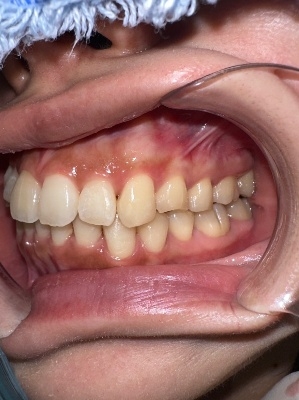

左側

右側

術前口腔内写真 正面観